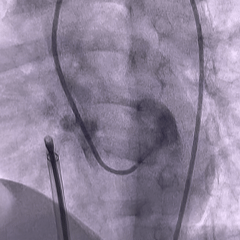

右盘展开

DSA下推出右盘,由于缺损隧道较长,为防止右盘展开后被牵拉入隧道内,术中全程保持钢缆张力使左盘稳定贴靠室间隔,再后撤鞘管展开右盘

造影确认封堵器位置正确

封堵器未锁定时造影,确认封堵器位置形态正确